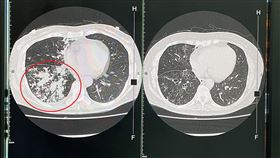

台中婦咳5年胸悶暴瘦 肺部驚見爆漿香腸

台中一名63歲謝姓婦人,近5年一直都有慢性咳嗽病史,...